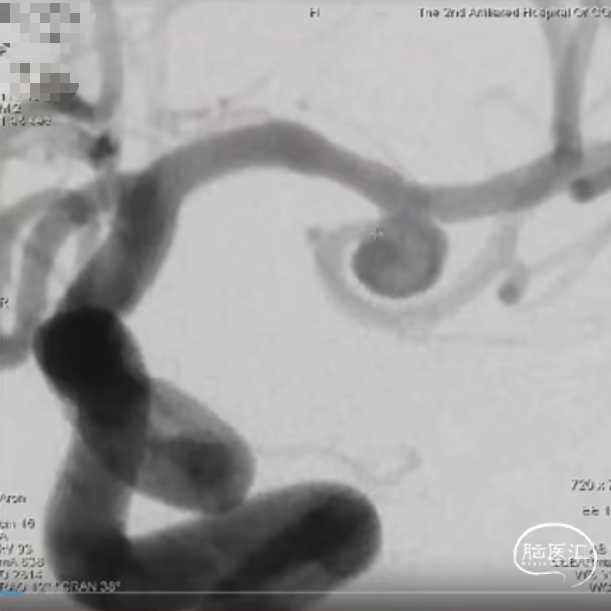

动脉瘤一:基底动脉末端动脉瘤,由左侧大脑后动脉与左侧小脑上动脉瘤夹角处动脉瘤形成且为不规则状;瘤体上有子囊形成,左侧小脑上动脉从近心端瘤颈处动脉瘤瘤体上发出,动脉瘤与载瘤动脉近直角。

经测量可得动脉瘤宽度平均值为8.88mm,动脉瘤最小高度为7.71mm,瘤颈约为4.03mm。参考尺寸选择表,选择WEB™ SL 10*5,VIA™ 33微导管。

缓慢推出WEB™从种子至萌芽状态,继续向瘤腔内远端缓慢推送WEB™至萌芽至开花间状态;将WEB™和VIA™送至瘤顶,固定WEB™推送杆回撤VIA™,WEB™完全释放。

经造影可见WEB™尺寸合适,贴合瘤壁,小脑上动脉分支,大脑后动脉分支等血流通畅。解脱后,再次造影和Dyna-CT评估,可见动脉瘤瘤腔内有明显造影剂滞留,小脑上动脉瘤显影良好,分支血管血流正常。